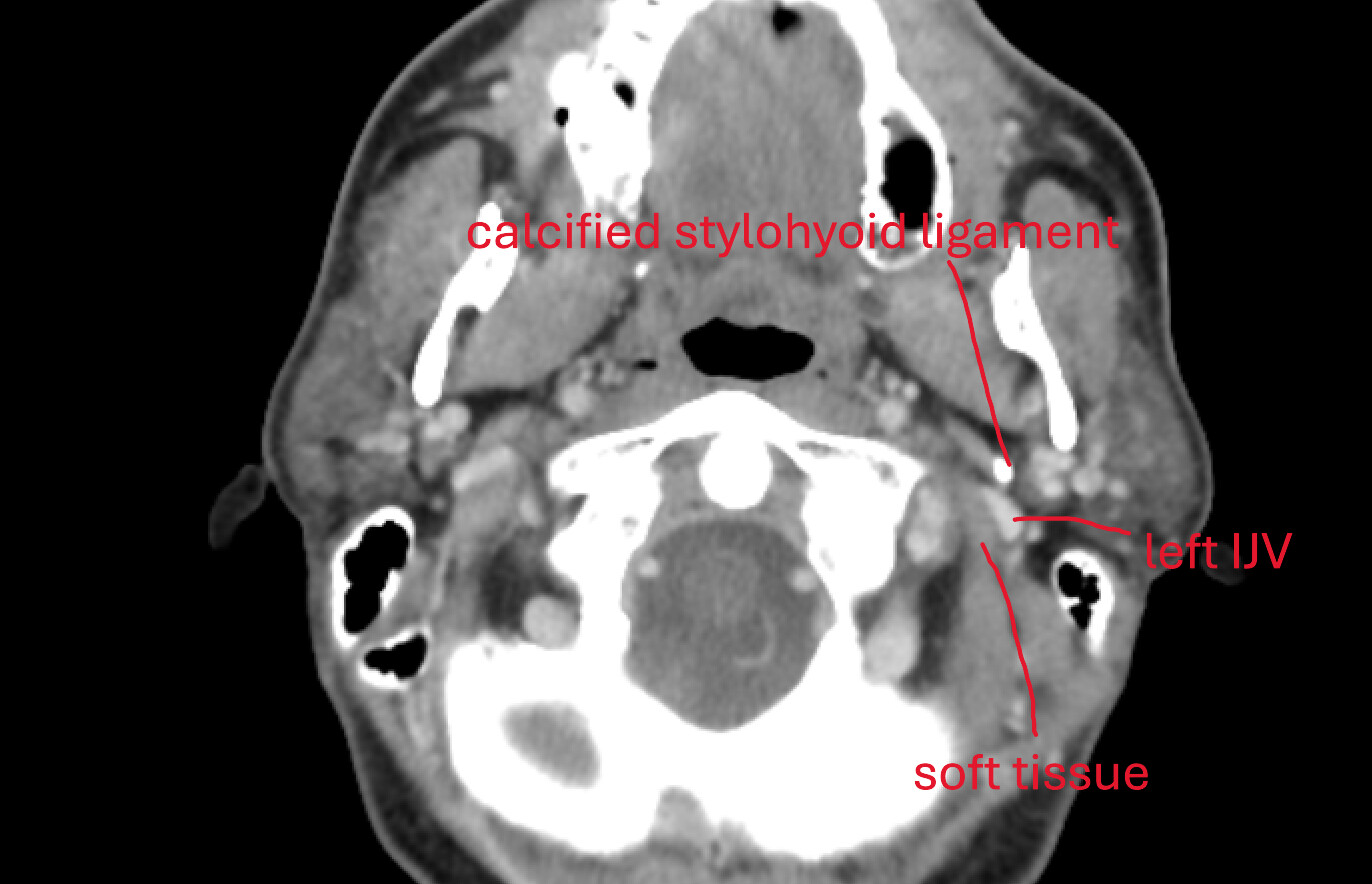

- Finally, my oral surgeon spotted something on the dental CBCT and asked me to check if I have ES. So, I did the CT for ES and it revealed a calcified portion of the stylohyoid ligament.

And, before we proceed, I literally looked at the 3D rendered CT today, and the calcified portion is only ~15mm, detached from styloid process, and about 1.5mm from C1. In the CT results, it says “partially calcified stylohyoid ligament, combined length 31mm” but the keyword there is “combined.”

Sagittal view. Calcified portion of stylohyoid ligament. There is a little bit more in another slice, but this is the most of it.

3D views – one is low-res from above CT, and another is high-res from a CT with 0.2mm slices (most detailed CT I’ve ever seen). Distance from C1 is measured at about 1.5mm, length of calcified portion is ~15mm and it is flatter on one side in the lower section, with a “bit” sticking out slightly.

I am also including some animated gifs of axial, sagittal, and coronal views of the calcification from the last CT scan.